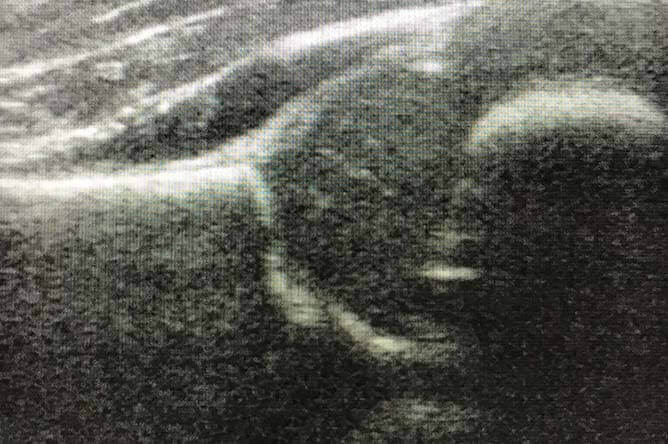

Ultraschall-Diagnostik

Für den optimalen Einblick: Mit der Ultraschall-Untersuchung des Bewegungsapparates können wir ohne jegliche Strahlenbelastung Muskeln, Sehnen, Bänder und Gelenke darstellen – eine sinnvolle Ergänzung oder sogar ein Ersatz zur Röntgen-Diagnostik. Anhand der Ultraschall-Bilder lassen sich Weichteilstrukturen optimal beurteilen. Ein weiterer großer Vorteil der Sonografie, wie die Ultraschall-Untersuchung auch genannt wird, ist die Möglichkeit der schadlosen Wiederholbarkeit. Dabei bietet die Ultraschall-Diagnostik nicht nur die Möglichkeit der Verlaufskontrolle, sondern auch die einer dynamisch-funktionellen Untersuchung.